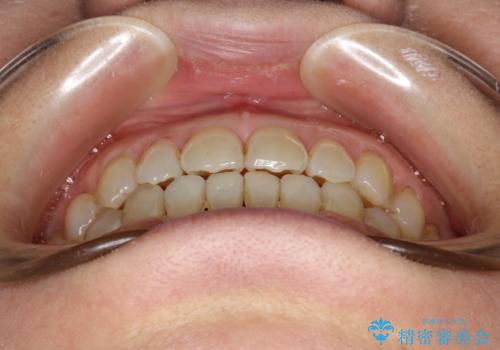

前歯の隙間 インビザラインによる目立たない成人矯正

- 前歯の隙間を気にされて来院されました。

インビザラインにて、目立たずに矯正治療を行うこととしました。

歯と歯の間にある隙間を閉じるのは、インビザラインでもしっかり治療できます。